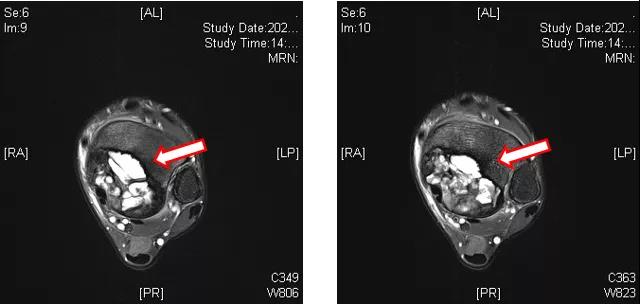

地舒单抗治疗后,复查左踝MRI提示:左侧胫骨内侧髁关节面下占位性病变,与2020-09-03 MRI对比,胫骨远端病变内T2WI高信号范围减小(图4~6)。

图4:左踝MRI(地舒单抗治疗后)

图5:左踝MRI(地舒单抗治疗后)

图6:左踝MRI(地舒单抗治疗后)